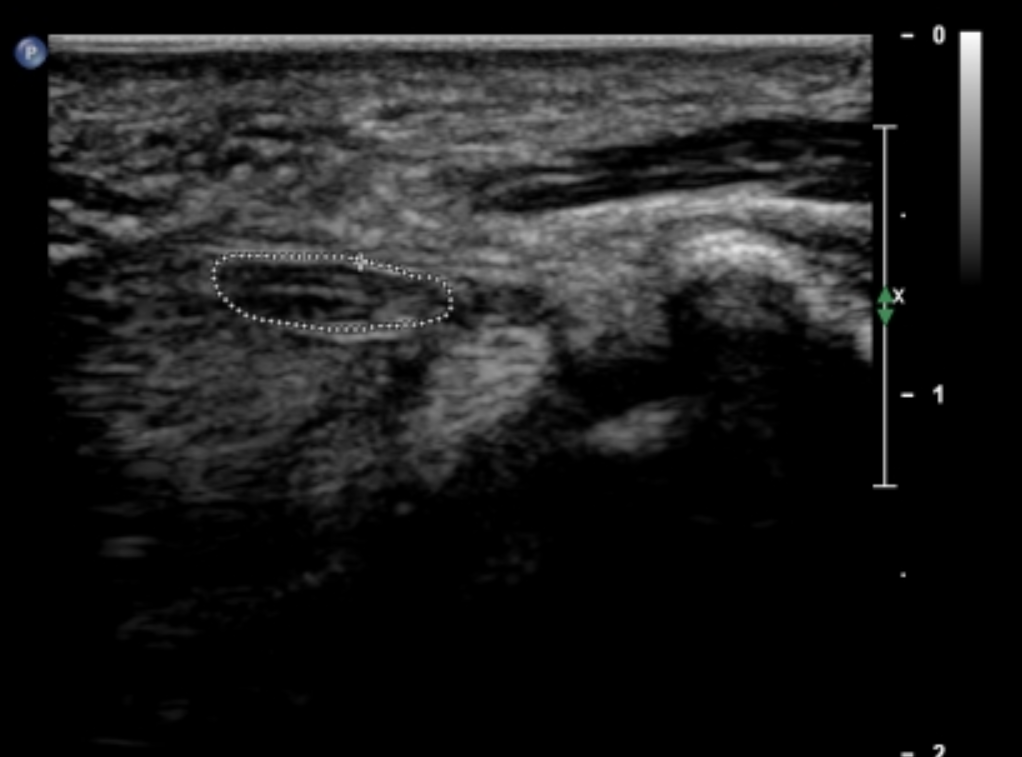

1️⃣ Pole przekroju poprzecznego nerwu (CSA)

To najważniejszy parametr ilościowy.

- nerw prawidłowy:

• część proksymalna ~9–11 mm²

• część dystalna ~8–9 mm² - nerw patologiczny:

• ≥14–16 mm² → II stopień

• świadczy o obrzęku uciskowym

Różnica między częścią proksymalną a dystalną (gradient) jest kluczowym wskaźnikiem ucisku.

2️⃣ Zwiększenie wymiaru AP nerwu

Zwiększenie grubości nerwu w wymiarze przednio-tylnym:

- prawidłowo: ~1,8–2,1 mm

- patologicznie: ≥2,5–2,6 mm

To cecha obrzęku pęczkowego i przeciążenia nerwu.